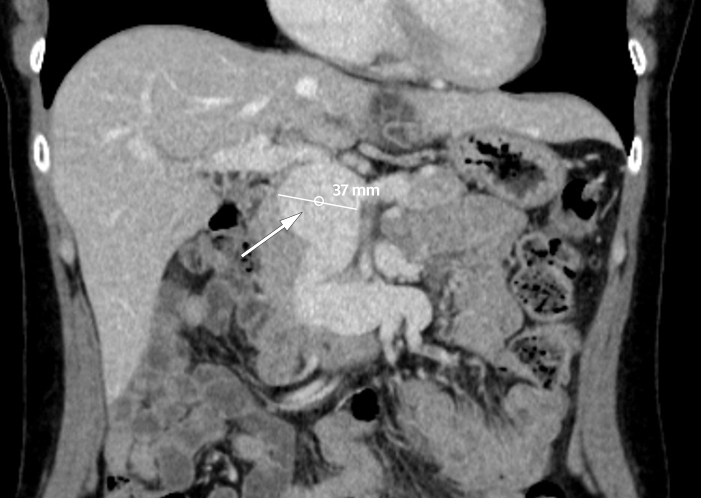

CT-bildet viser et 37 mm stort aneurisme i portvenen, inklusive stammen til vena mesenterica superior og grener til denne. Pasienten var en kvinne i 40-årene med tidligere anoreksi. Hun hadde i fire uker vært plaget av diffuse magesmerter og tidlig metthetsfølelse. Klinisk undersøkelse og orienterende blodprøver hos fastlege, herunder leverprøver, viste normale funn, og hun ble henvist til CT.

Portveneaneurisme er en sjelden tilstand (1). Om lag 200 tilfeller er beskrevet i litteraturen, og kunnskapsgrunnlaget bygger på kasuistikker og pasientserier. Det defineres som en fokal dilatasjon i portvenen, over 15 mm ved normal lever og over 19 mm ved levercirrhose (2–3). Aneurismet er oftest lokalisert til portvenens hovedstamme, dernest ved portvenedelingen (1). Tilstanden kan være medfødt eller ervervet, da oftest grunnet portal hypertensjon sekundært til levercirrhose (1).